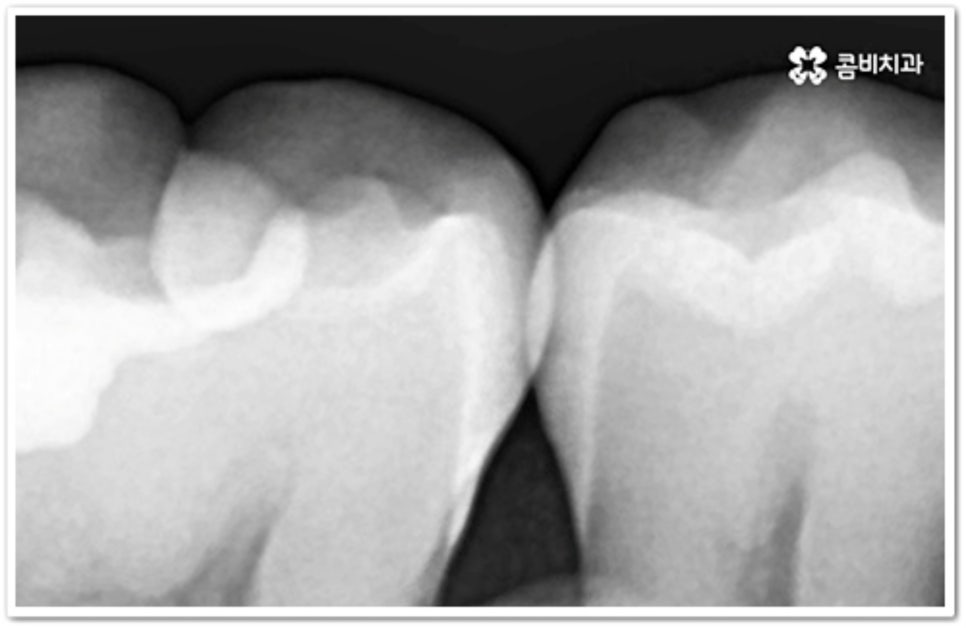

충치는 시간을 두고 단계적으로 진행하는 구강 질환이기 때문에 초기에 발견하여 빠르게 대처해 주는 것이 구강 건강을 위해 보다 바람직한 방법이라 할 수 있습니다. 흔히 우리가 충치라고 부르는 치아 우식증은 발생 위치에 따라 두 가지 종류로 나눌 수 있는데요. 보통 위아래 치아가 마주보는 교합면에 생기는 충치는 육안으로 발견할 가능성이 높고 접근이 용이하기 때문에 치료가 쉬운 편이지만, 치아 사이에 생기는 인접면 충치 는 맞닿은 치아로 인해 노출이 잘 되지 않기 때문에 발견도 어렵고 상황에 따라 치료할 때 기구를 손상 부위까지 닿게 하기 위해 치아 삭제가 많이 이루어져야 하는 경우도 있는 등 좀 더 까다로울 수 있어요.

치아의 구조를 살펴보면 안쪽의 무른 조직을 감싸고 있는 단단한 바깥쪽 법랑질은 교합면에서 가장 두껍고 잇몸쪽으로 갈수록 얇아지기 때문에 인접면에 생긴 충치의 경우 조금만 진행 되어도 손상이 내부 신경까지 보다 빠르게 번질 수 있어요. 신경치료를 받은 치아는 정상 치아에 비해 외부 충격에 취약해지므로 가능한 한 그 단계에 이르기 전에 적절한 치료를 받으실 필요가 있는데요.

인접면에 충치가 생겼을 때 치료 과정은 손상 정도에 따라 달라질 수 있는데 만약 아주 경미하다면 바로 레진으로 이를 수복할 수 있겠지만 치아 경계면이 무너졌다면 직접적인 레진 수복으로는 생리학적 형태를 재현하기 까다롭기 때문에 본을 떠서 외부에서 금이나 세라믹 보철물을 만들어 끼워넣는 간접적인 방법을 통해 도움을 받을 수 있어요. 환자분들의 상황에 따라 치아 일부만 수복해야 할 때는 인레이 치료를 하고 손상이 크면 신경치료를 한 후 필요시 내부에 기둥을 세우고 치아 전체를 다듬어 씌우는 크라운 치료를 이용하게 될 거예요.